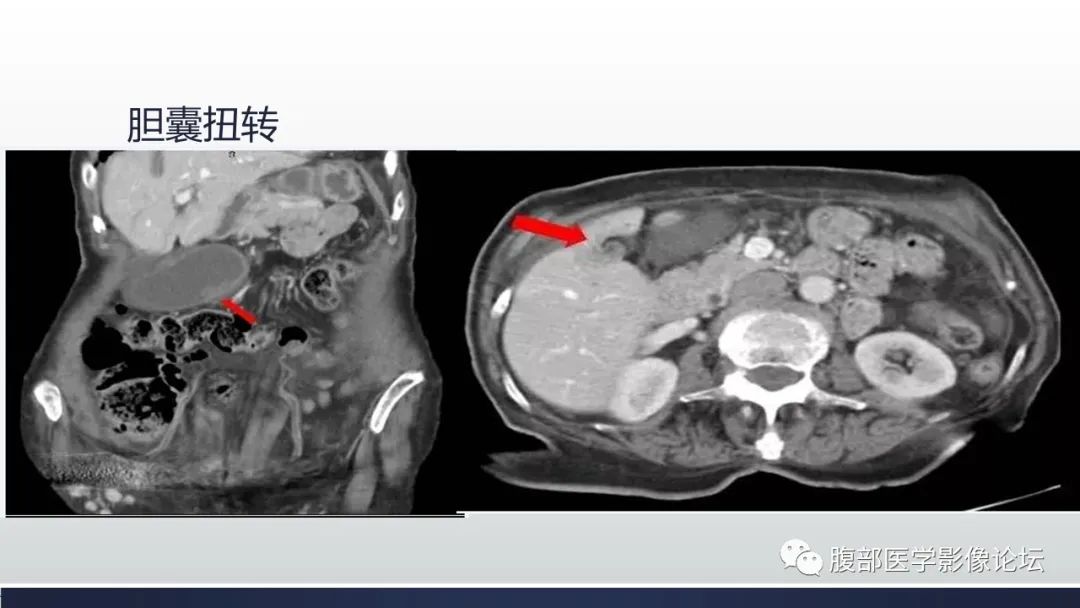

【病例】胆囊管状腺瘤1例CT及MR影像表现-7

【病例】胆囊管状腺瘤1例CT及MR影像表现-8